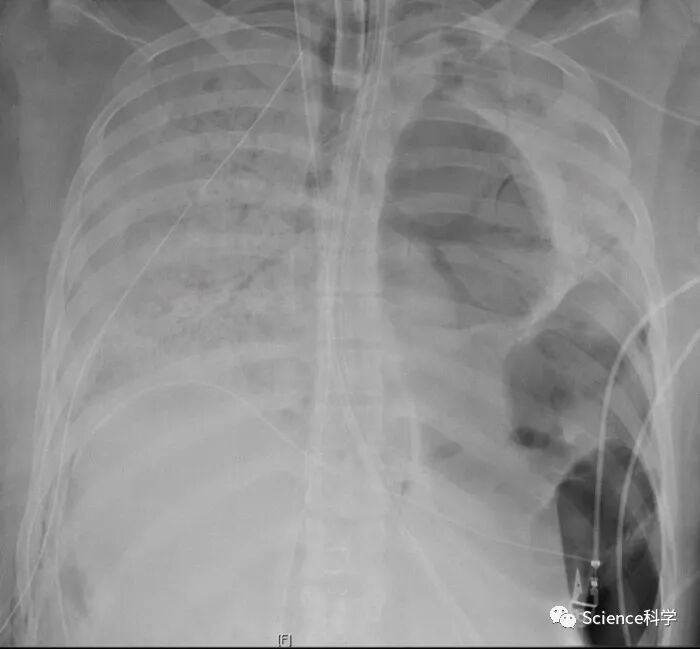

在一名新冠肺炎患者肺部严重受损并只能靠呼吸机维持生命后,美国医生们首次对一名COVID-19患者进行了先进的肺移植手术。这场风险很大的手术是在美国西北纪念医院进行的,专家们得出结论,如果没有两个新肺,病人将没有生存的机会。

移植手术是在对于这个特殊的COVID病人(一位20多岁的西班牙裔女性)进入重症监护室六周后进行的。这涉及到由呼吸机和体外膜氧合(ECMO)的机器支持,有效地接管了她受损的心脏和肺部的工作。医院说,即使有这种支持,"到6月初,病人的肺部出现了不可逆的损伤"。